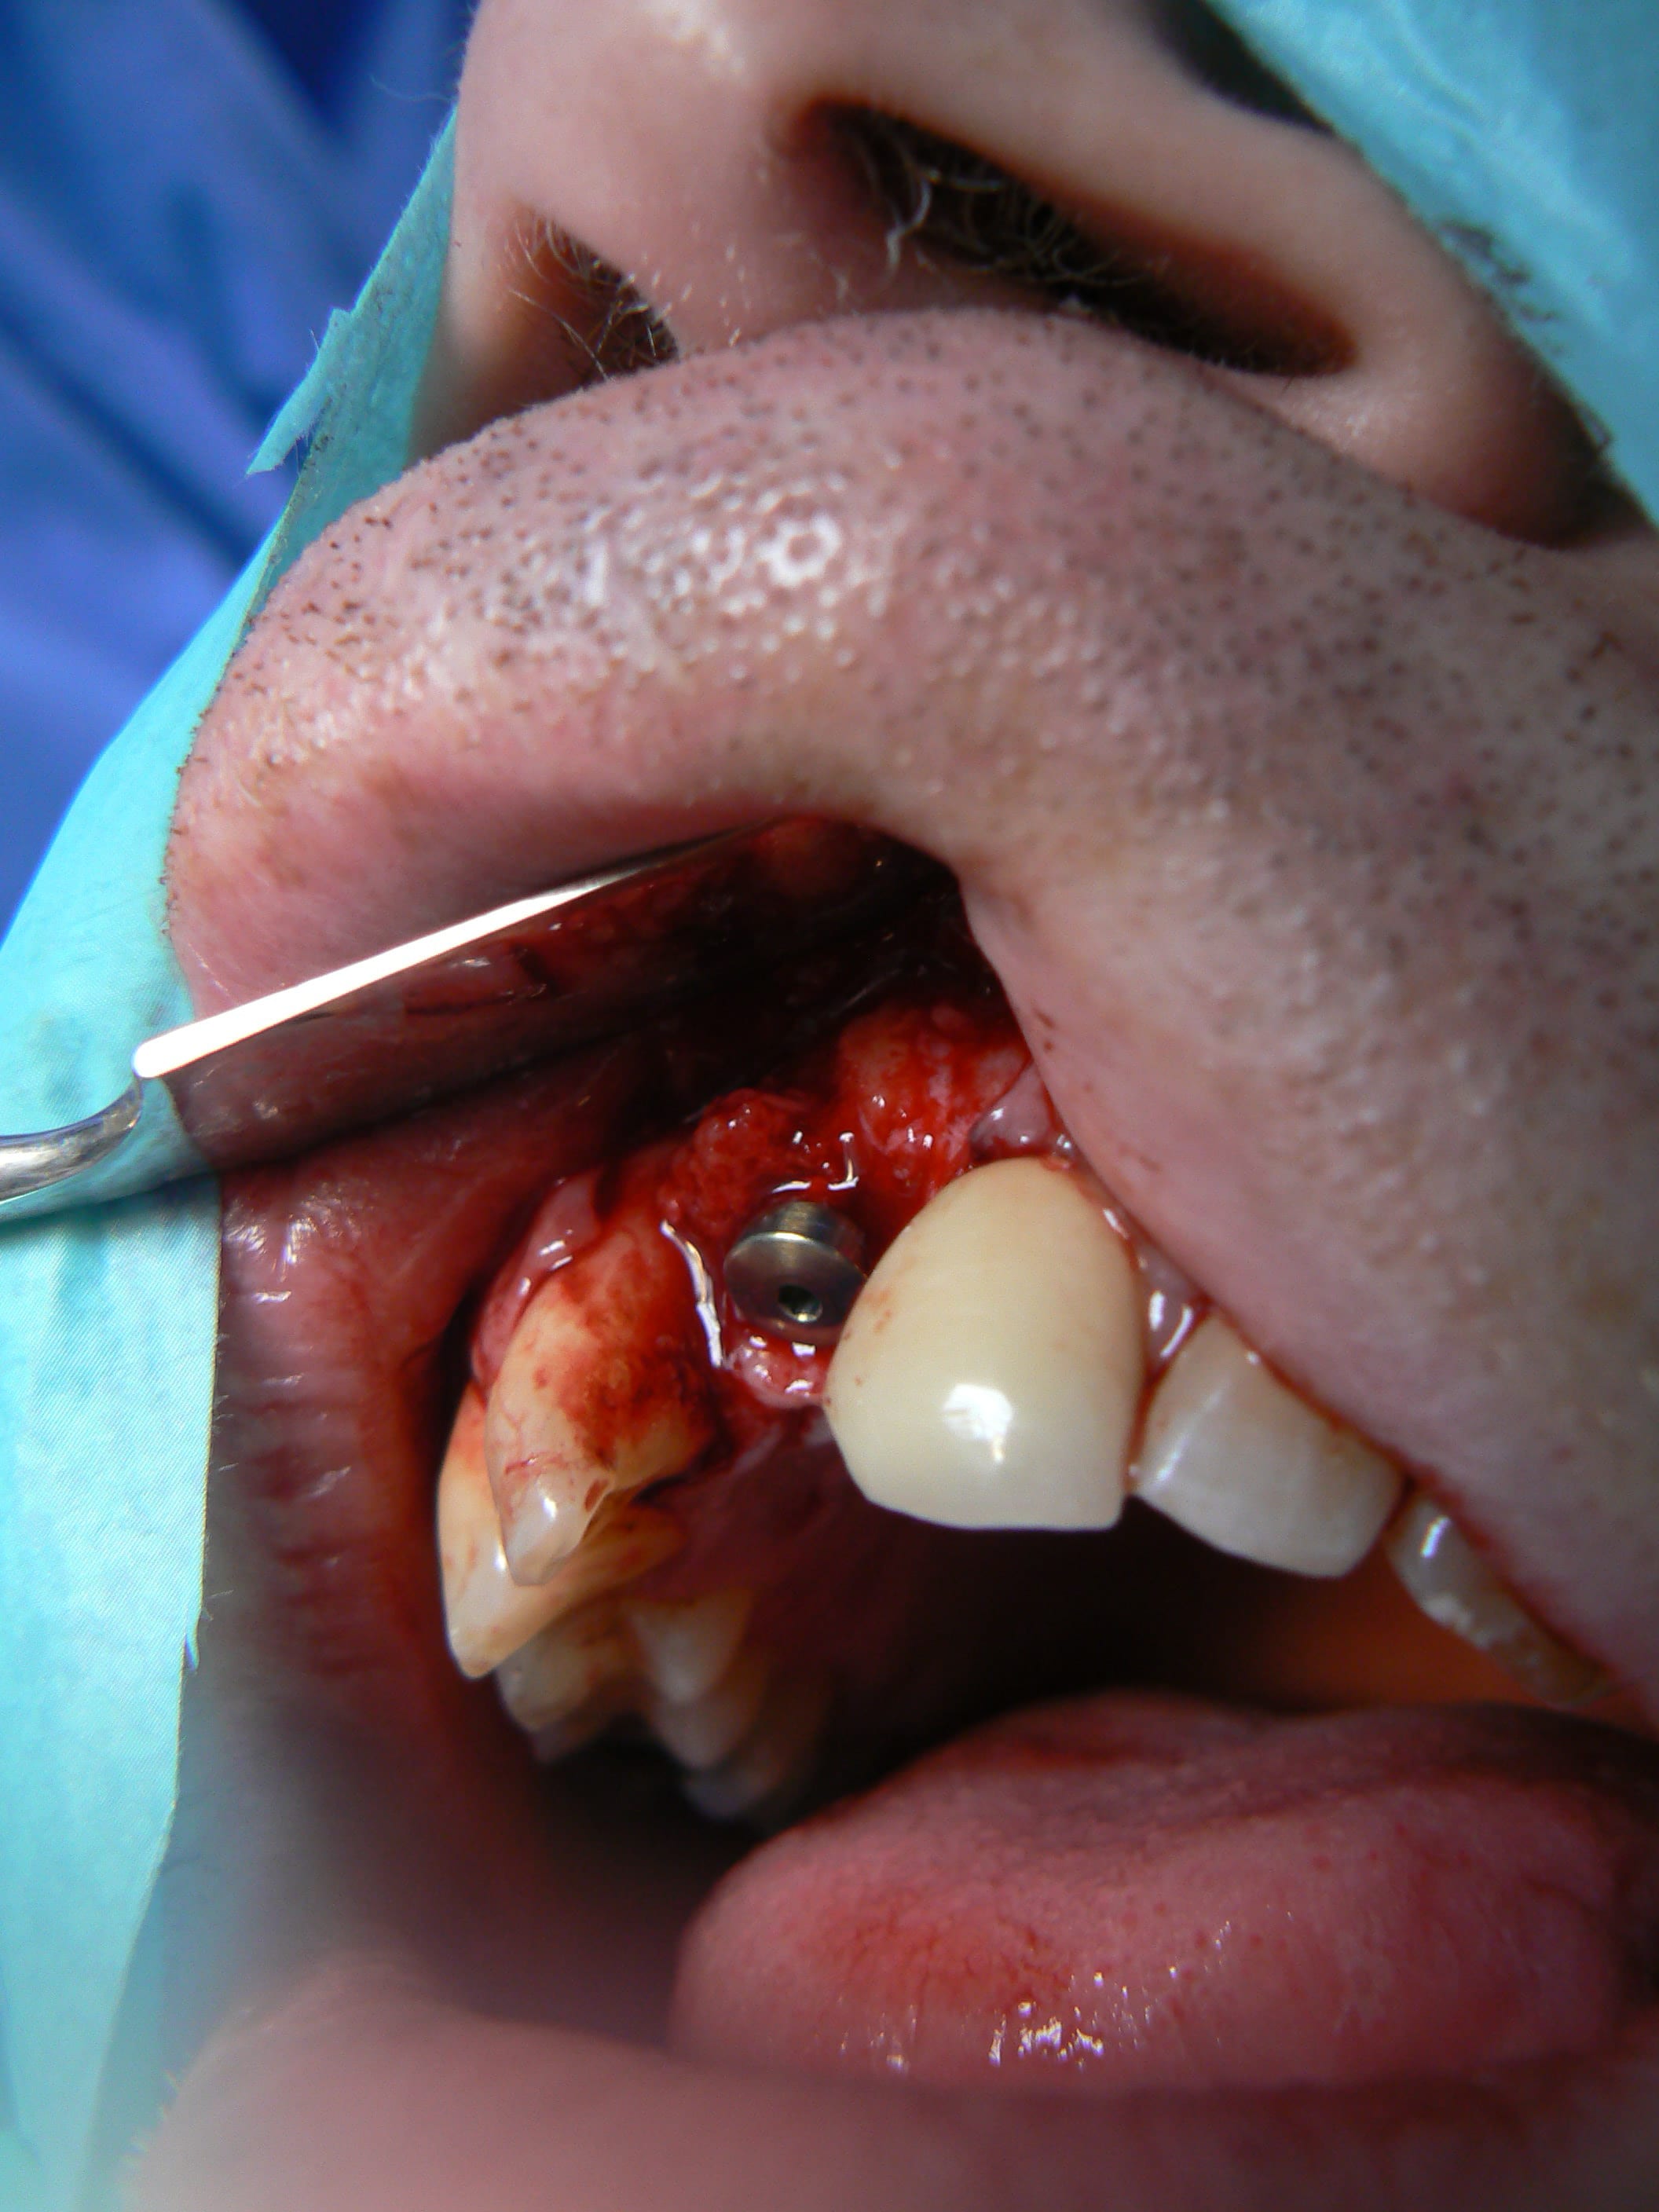

> Ci joint cas avec biobank, très bonne stabilité et consistance a la réouverture

> a 9 mois.

j'ai retrouvé, mais c'est le correspondant qui à posé l'implant et les photos sont pas top :(

j'essaie d'envoyer si ça marche